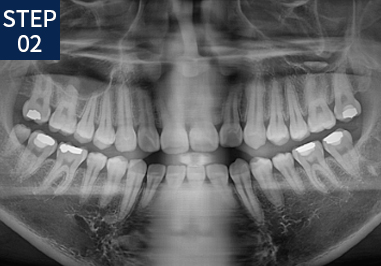

당신만을 위한 치아교정 1:1 프로세스

• 기초 조사 및 상담

• X-RAY/구강/안면촬영

• 치열을 위한 인상채득

• 분석 및 치료계획 수립

• 진단 및 상담